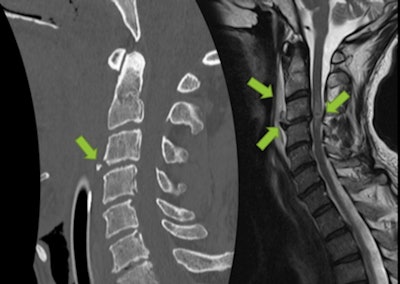

Cervical pain in 57-year-old man after ski fall. Fracture of base of C2 odontoid process with lesion of anterior longitudinal ligament, prevertebral hematoma, and narrowing of left vertebral foramen, without arterial dissection.Even in the absence of skull or cervical fractures, patients may present with vascular injuries, so a high degree of suspicion is required from the examiner. Mechanisms of hyperflexion, hyperextension, acceleration, or deceleration should raise a red flag and elicit a more comprehensive investigation. In the acute setting, CT angiography is preferred over MR angiography if the patient presents with one of these mechanisms and/or skull base fractures and/or cervical fractures involving the vertebral foramina.

Traumatic injury in 53-year-old man after ski fall (GCS 6/15 onsite). Normal initial brain CT scan, but clinical evaluation was impossible due to intubation onsite. CT revealed teardrop fracture on C3 and subtle retrolisthesis of C3 over C4, suggesting hyperextension discoligamentous injury. MRI confirmed rupture of anterior longitudinal ligament, discal extrusion into prevertebral space, and a hemorrhagic spinal contusion at C3-C4 level. Patient was found to be tetraplegic after extubation."The mechanism of injury determines the distribution of injury levels and thus influences the degree of neurologic deficit," they commented.